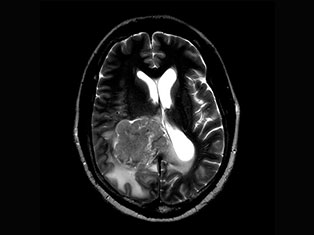

Brain Tumors

A brain tumor is a mass or growth of abnormal cells in your brain. Many different types of brain tumors exist. Some brain tumors are noncancerous (benign), and some brain tumors are cancerous (malignant).